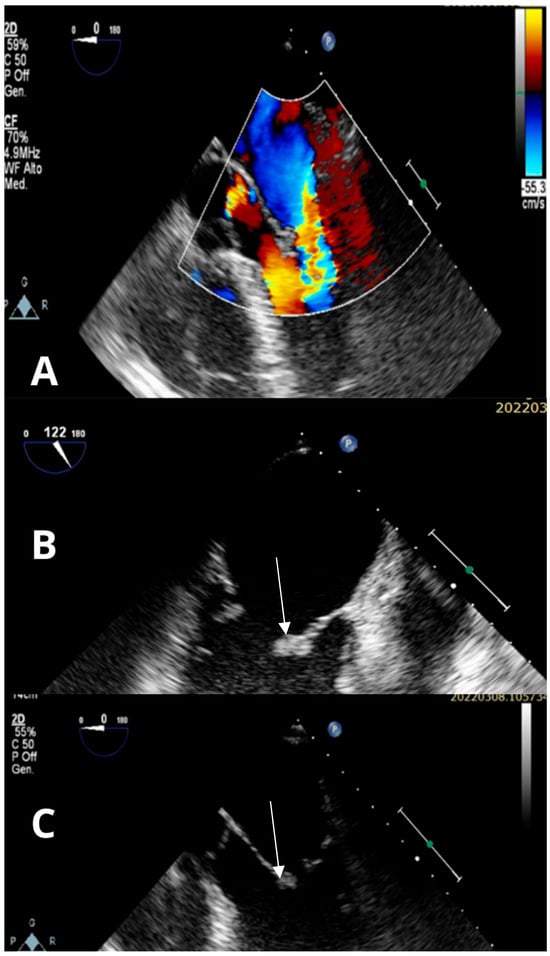

Background and Clinical Significance: Trousseau’s syndrome, characterized by recurrent thromboembolic events and non-bacterial thrombotic endocarditis, represents a severe paraneoplastic condition associated with poor prognosis in cancer patients. Due to the growing life expectancy of cancer patients, Trousseau’s syndrome is becoming more frequent. Consequently, risk of thrombosis and bleeding assessment, as well as early diagnosis and opportune therapy will gain importance. Case Presentation: We describe a case of a 63-year-old Caucasian male presenting with ischemic stroke. During management, he developed a mitral valve marantic endocarditis, and finally the diagnosis of pulmonary adenocarcinoma was performed. The case description is followed by a brief review of the relevant literature on the condition. Discussion and Conclusions: This case highlights the complexity of diagnosing and managing Trousseau’s syndrome. Early recognition, appropriate anticoagulation strategies, and the need for multidisciplinary management are crucial to improve the outcomes and the quality of life for cancer patients. Full article